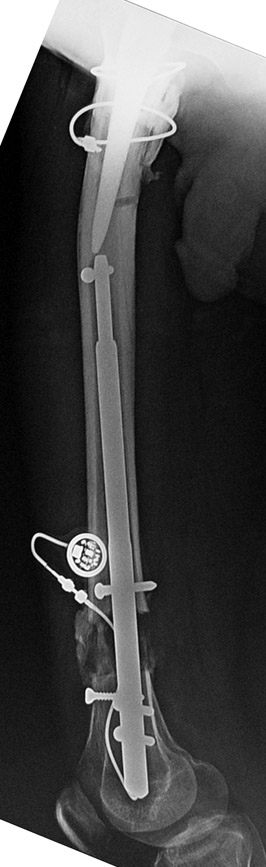

Since 2005 Dr. Mehmet KOCAOGLU is the first most Fitbone operating surgeon in TURKEY. He established the center of excellence for Fitbone surgeries in Istanbul. Fitbone comprises a telescopic nail implant that can extend, powered by an electric motor and controlled by a receiver with an antenna that is buried under the skin; the receiver in turn is controlled by a hand-held radio-frequency transmitter. The procedure for lengthening the lower leg is as follows:

A two-centimetre incision is made at the patient’s knee, and a rimmer is used to create enough space in the bone for a stainless steel nail.

The bone is cut about 14 cm below the knee from the inside with an internal saw. The stainless steel nail is held in place by two screws. The top of the nail is attached to a tiny, plastic-encased receiver that is placed under the skin. The patient controls the lengthening process. By pushing a button on the transmitter when it is placed against the antenna, the built-in motor extends the nail one millimetre per day. When the leg has grown to the desired length, lengthening stops, and the bone is allowed to solidify. The device can be removed about two years after the initial surgery. This procedure, however, comes at a price. While the Ilizarov external fixator costs approximately USD$4,000, and the ISKD implant about USD$8,000, the Fitbone device carries a price tag of roughly USD$15,000 (all prices exclusive of surgery costs).